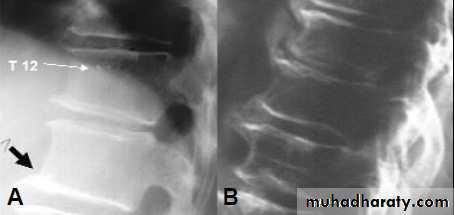

Fractures due to bone fragility are the most common manifestation.

Back pain, height loss, kyphosis and discovery of radiological osteopenia during evaluation for other conditions are also important.

Osteoporotic fractures can affect any bone but the most common sites are the forearm (Colles fracture), spine (vertebral fractures) and femur (hip fracture).